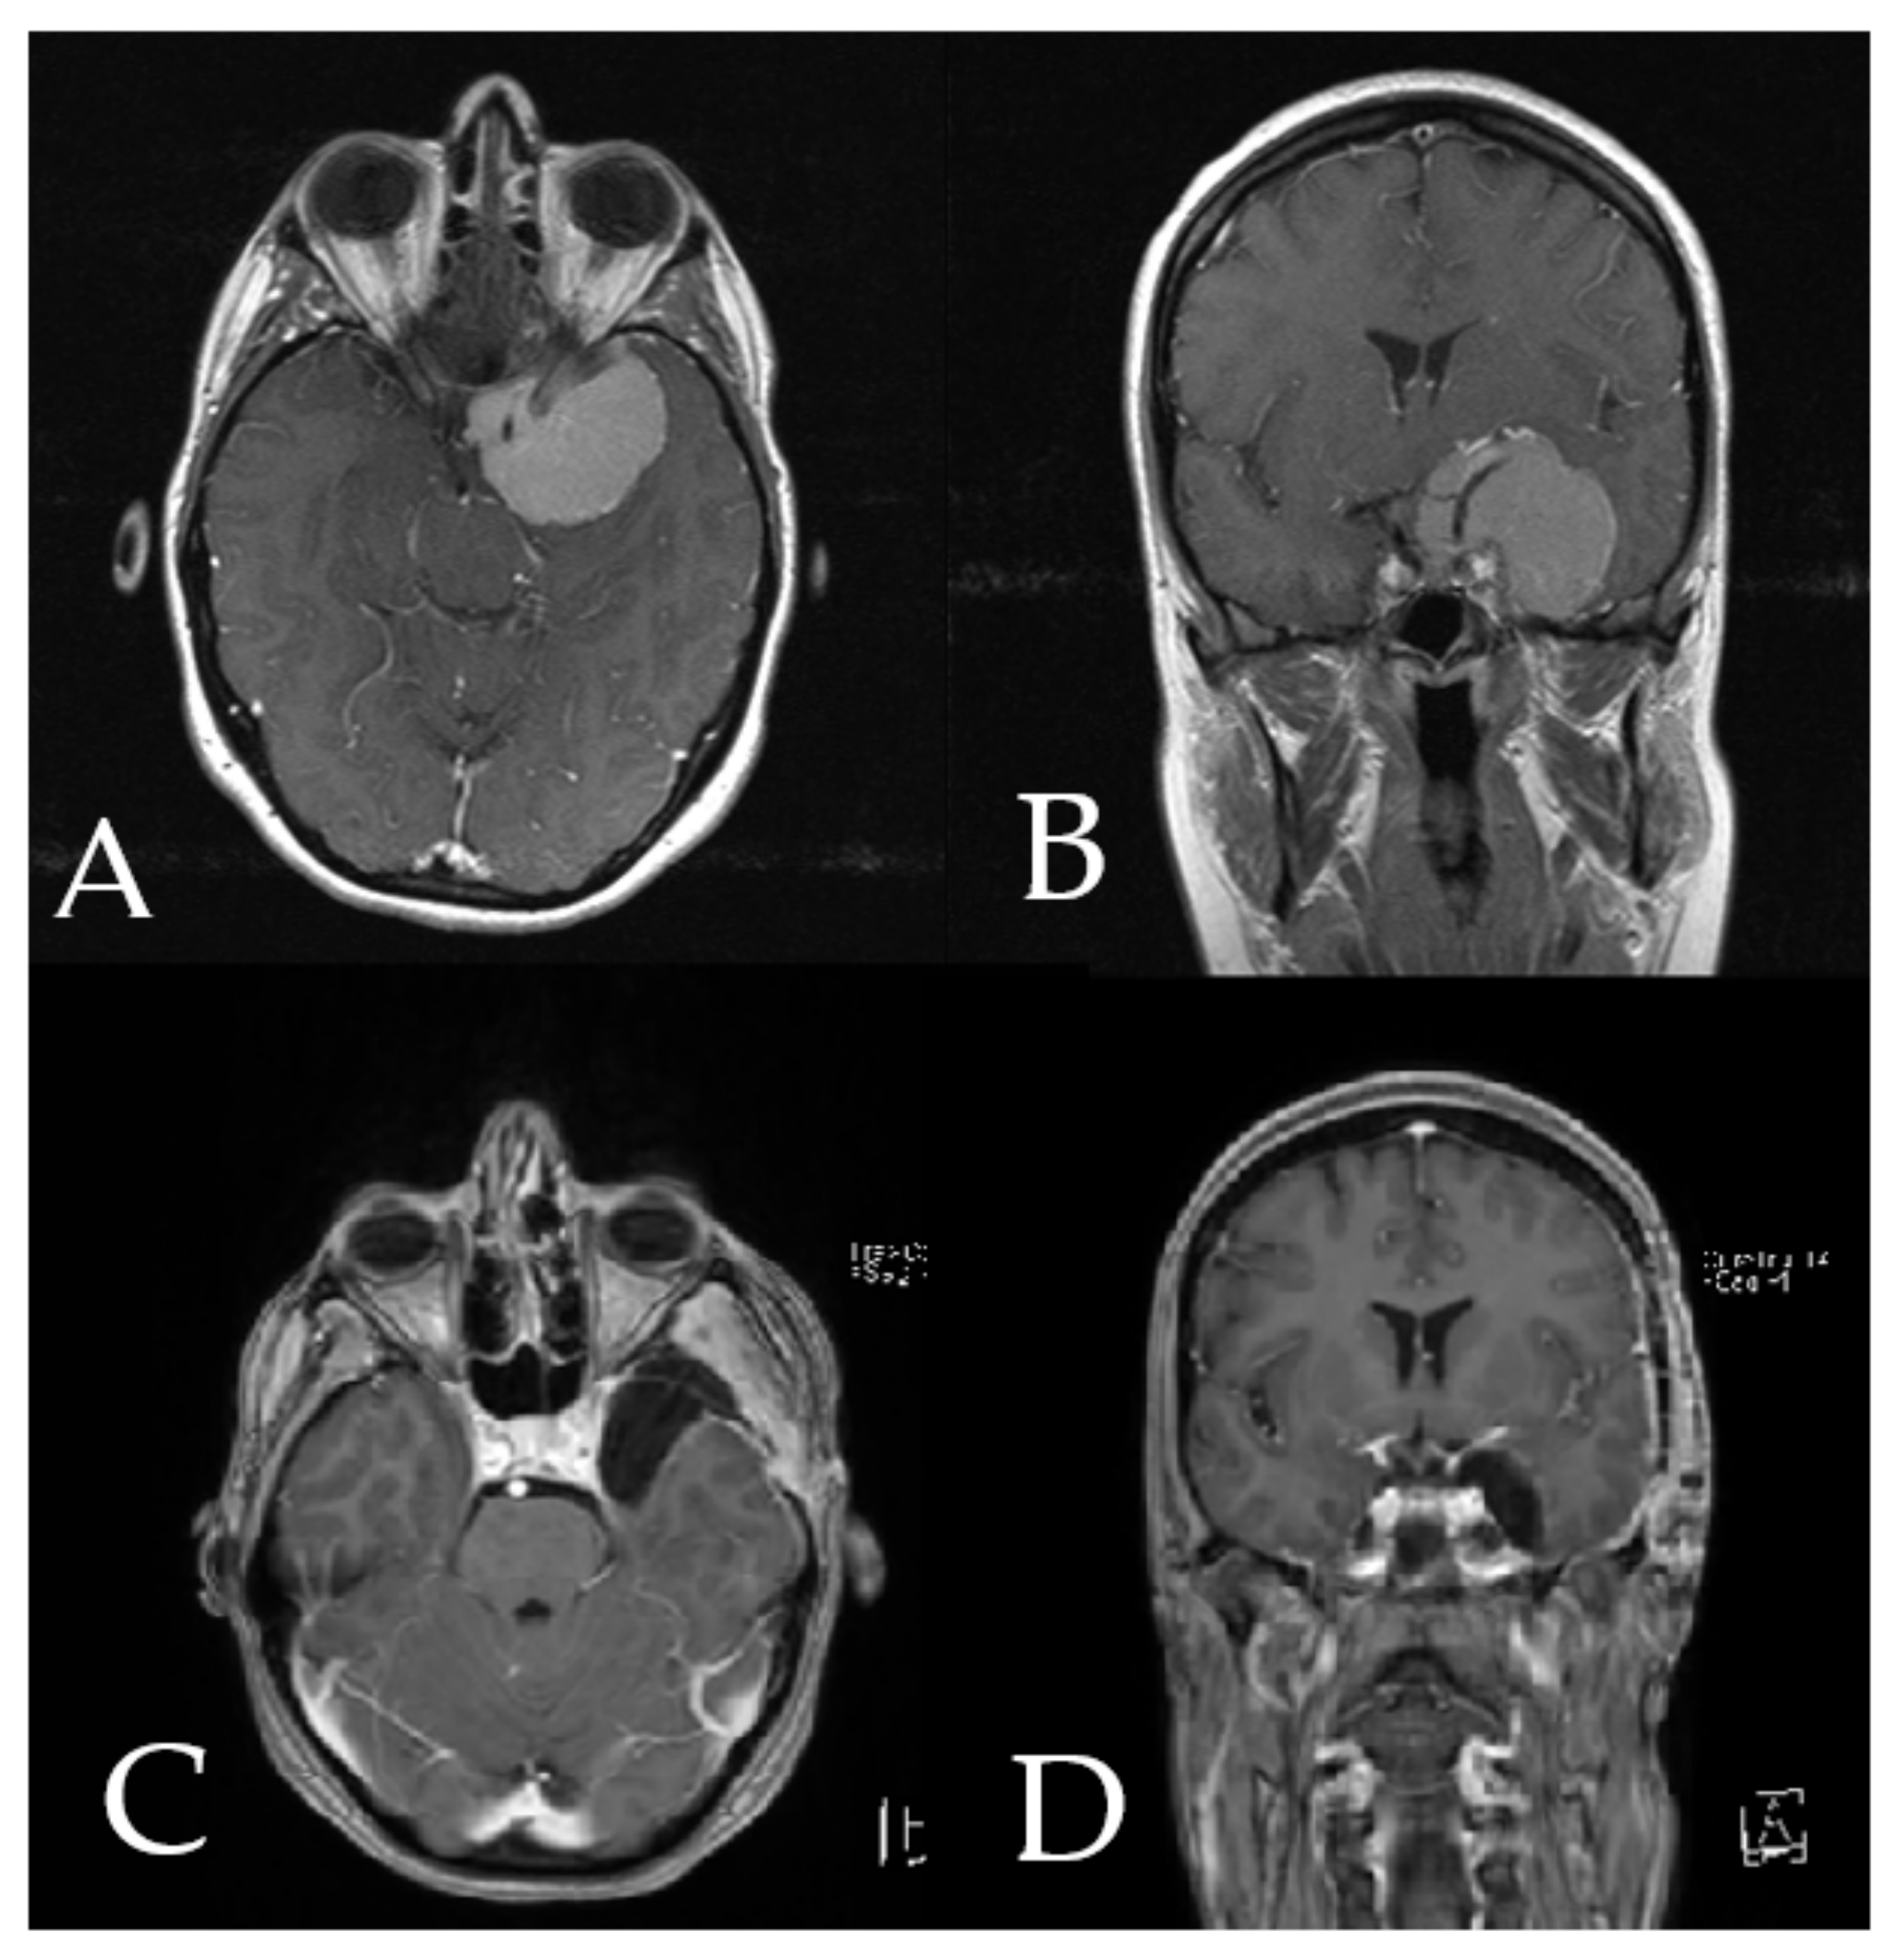

Illustrative Cases